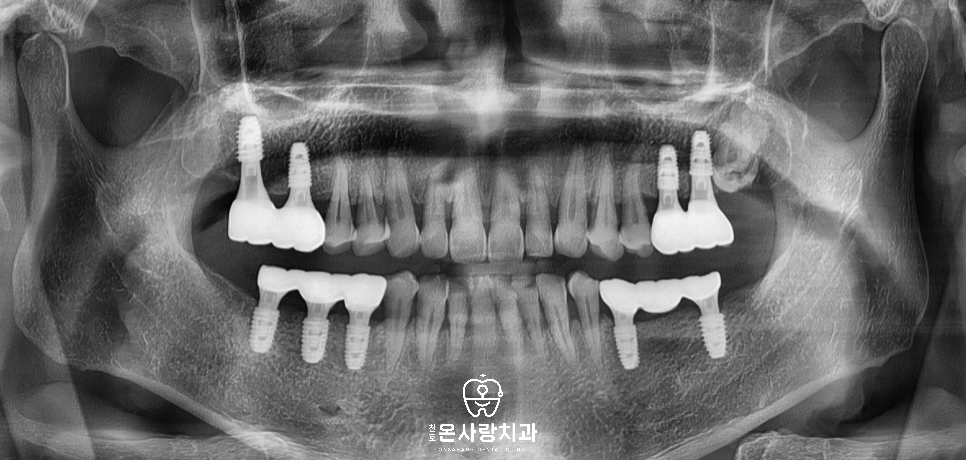

이번에 저희 천호역치과 천호온사랑치과를

내원해주신 환자분은

처음에 내원하셨을 때 큰어금니 부분의

치아가 모두 상실된 상태였습니다.

양측 어금니 위아래가 이미

없었기 때문에 씹을 때

큰 역할을 담당하는 치아의 부재로 인해서,

저작 기능이 거의 소실되어 있어

장기적인 교합 안정과 양측 균형

회복을 목표로 계획을 세웠습니다.

오른쪽 위 아래, 왼쪽 위에는

필요한 치아에 맞추어

총 9개의 임플란트를 식립하였습니다.

왼쪽 아래에는 2개의 임플란트를 심은 뒤

가운데 인공치아를 넣어 브릿지로

완성하였습니다.

이러한 브릿지는 저작력의

좌우 균형을 맞추고 턱관절 부담을

줄이는 데 중점을 두었습니다.